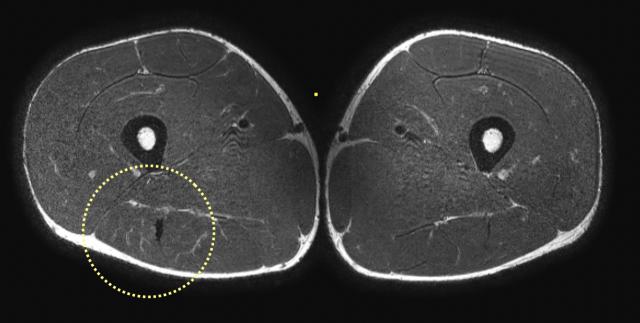

Chỉ dựa vào các hình ảnh coronal đơn thuần, đôi khi khó có thể phân loại chính xác mức độ biến dạng. Cần sử dụng các hình ảnh axial để quan sát kỹ hơn.

Trên các hình ảnh axial này, có thể thấy tăng tín hiệu và dày lên của gân cơ nhị đầu đùi bên trái (vòng tròn chấm vàng) khi so sánh với bên không bị tổn thương (vòng tròn chấm trắng).

Trong trường hợp này, tổn thương gân cơ nhị đầu đùi được phân loại là tổn thương bán phần độ 3, do chiều dài vùng phù nề > 15cm (đường chấm trắng) và chiều dài đoạn gân biến dạng > 5cm (đường chấm vàng).